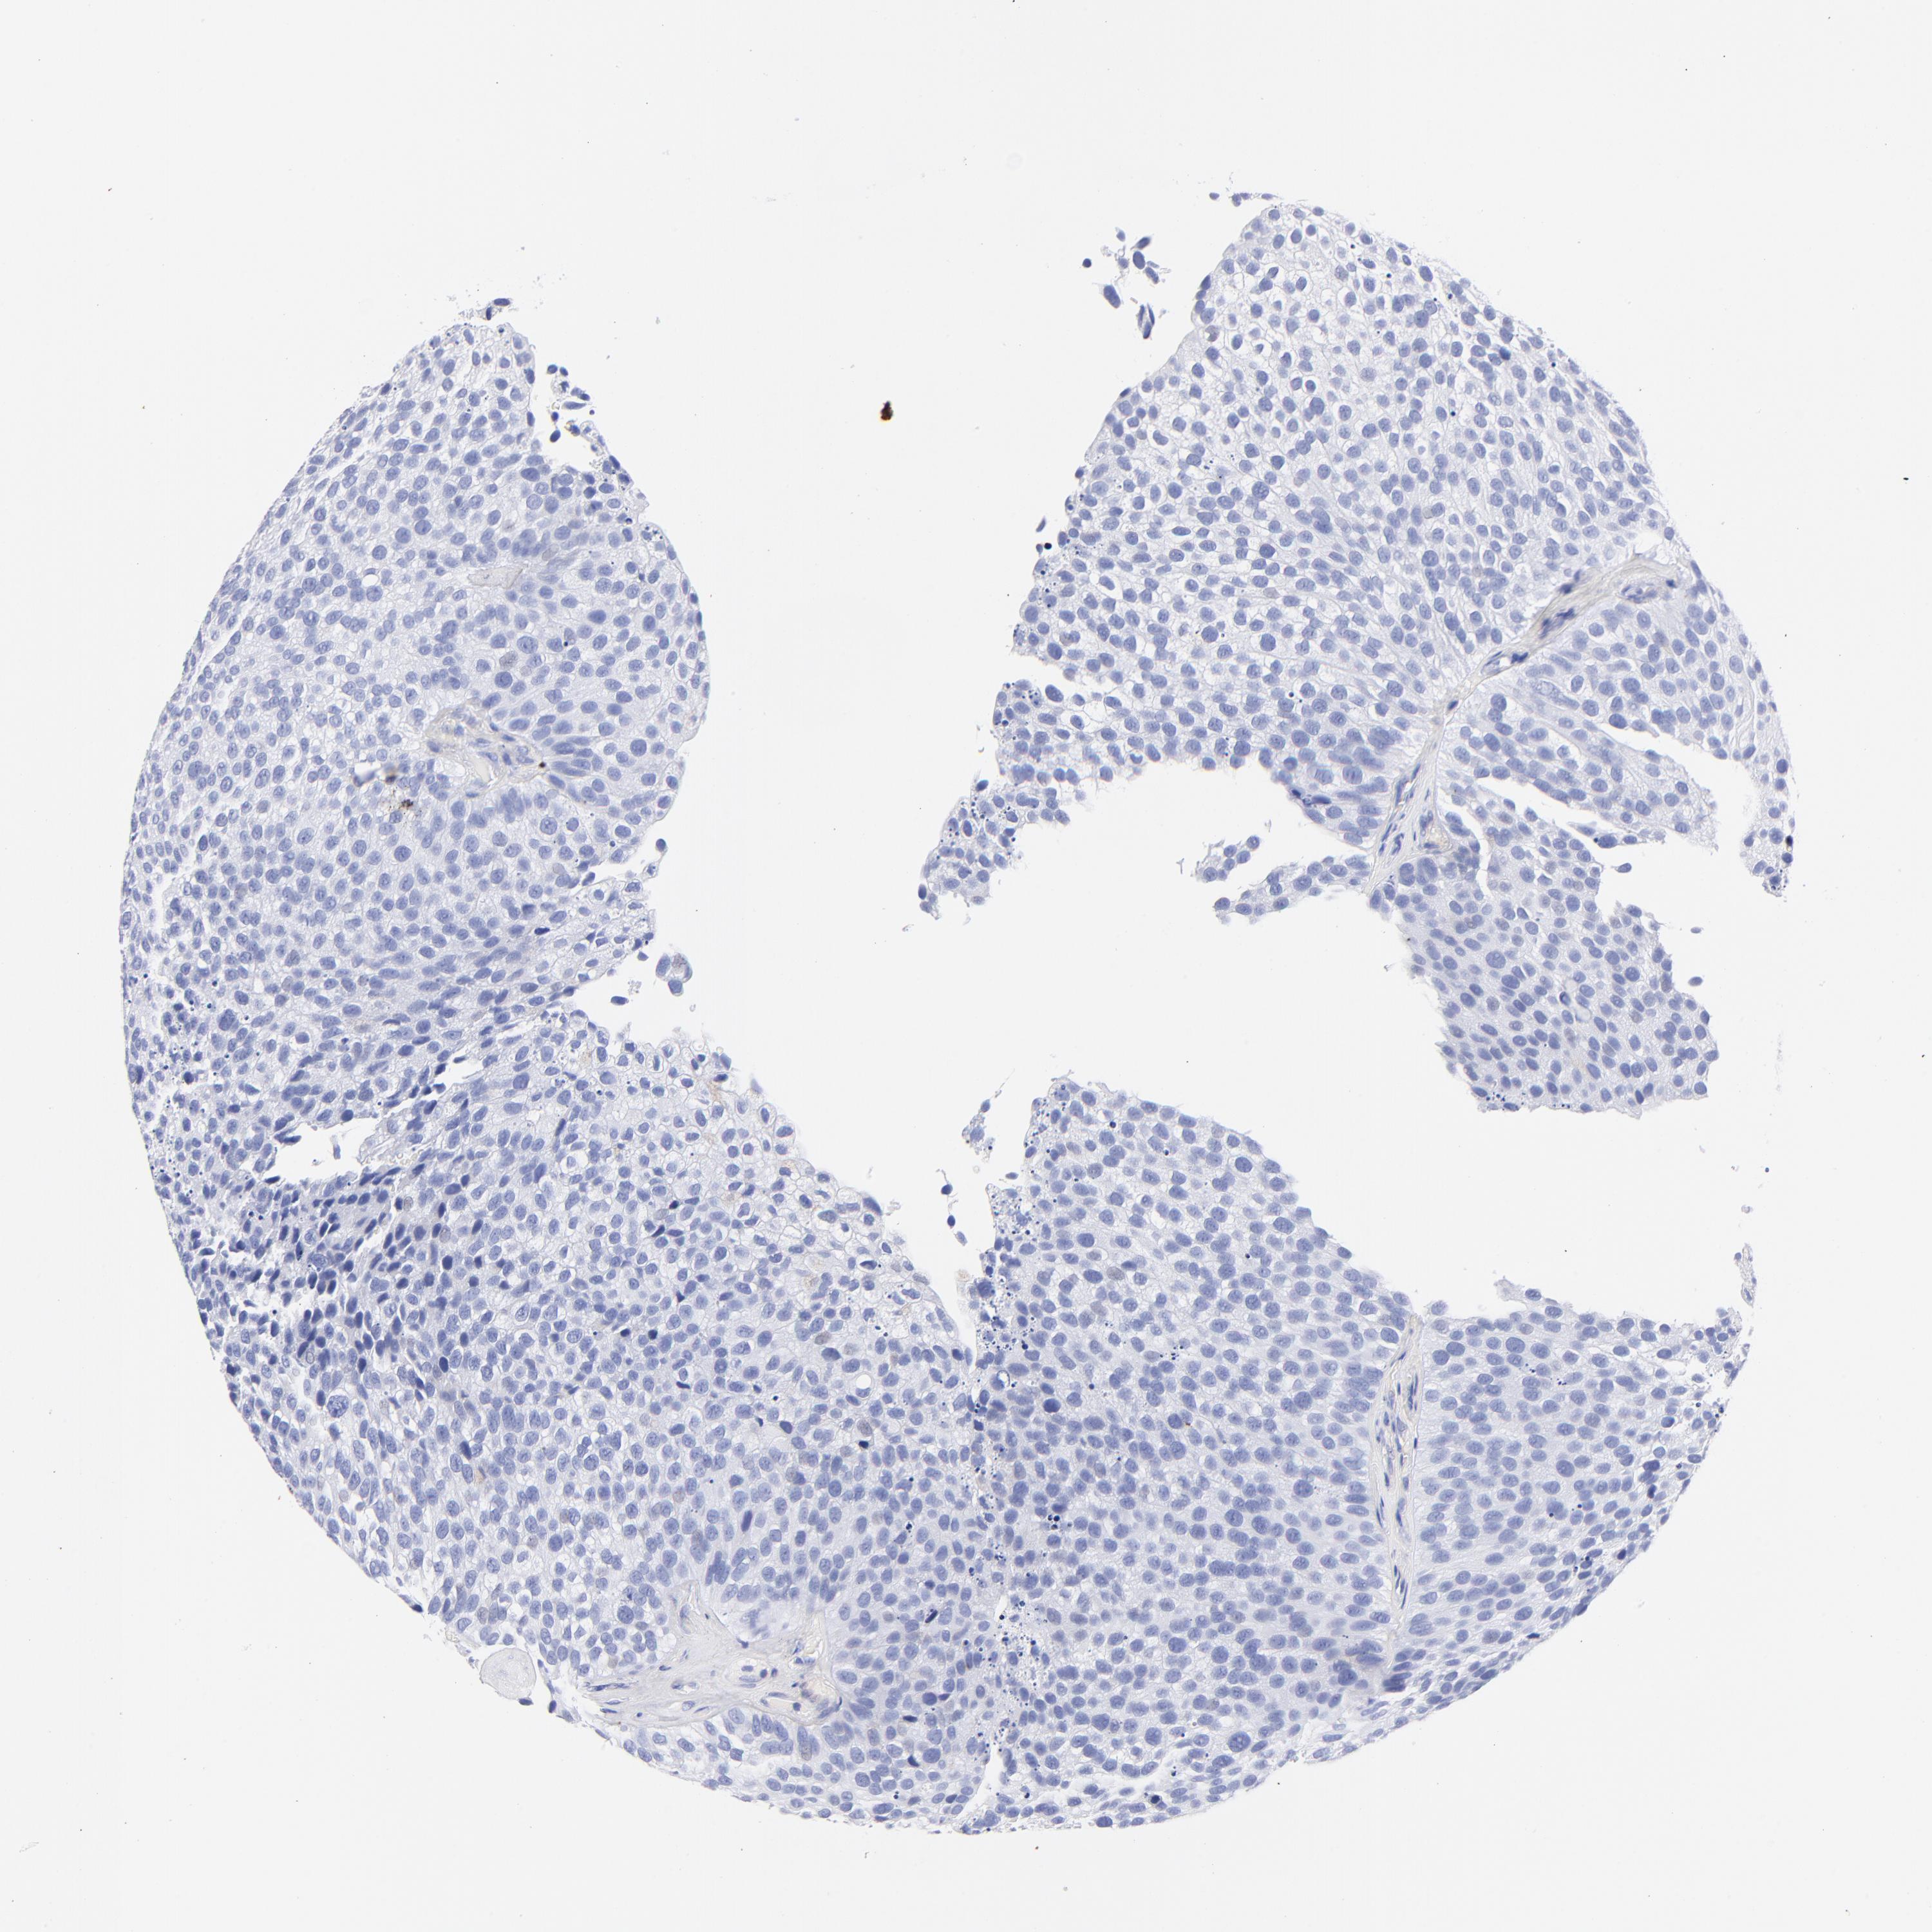

UROTHELIAL CANCER - Protein expressioni

A mouse-over function shows sample information and annotation data. Click on an image to view it in a full screen mode. Samples can be filtered based on level of antibody staining by selecting one or several of the following categories: high, medium, low and not detected. The assay and annotation is described here.

Note that samples used for immunohistochemistry by the Human Protein Atlas do not correspond to samples in the TCGA dataset.

Antibody stainingi

Antibody staining in the annotated cell types in the current human tissue is reported as not detected, low, medium, or high, based on conventional immunohistochemistry profiling in selected tissues. This score is based on the combination of the staining intensity and fraction of stained cells.

Each image is clickable and will lead to virtual microscopy that enables deeper exploration of all samples and also displays staining intensity scores, fraction scores and subcellular localization as well as patient and tissue information for each sample.

Antibody HPA003074

Staining

High

Medium

Low

Not detected

Intensity

Strong

Moderate

Weak

Negative

Quantity

>75%

75%-25%

<25%

None

Location

Nuclear

Cytoplasmic/membranous

Cytoplasmic/membranous,nuclear

Urothelial carcinoma, High grade

Urothelial carcinoma, Low grade

Adenocarcinoma, NOS